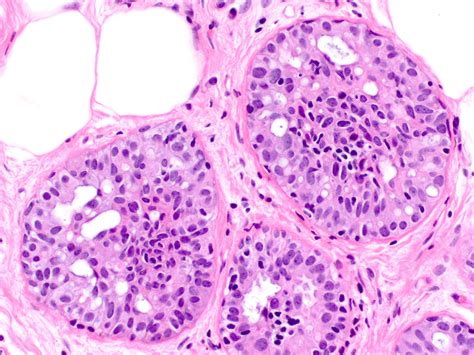

hyperplasia ductal usual pathology outlines epithelial atypia without immature

hyperplasia ductal usual pathology epithelial outlines intraductal atypia without fenestrated spaces